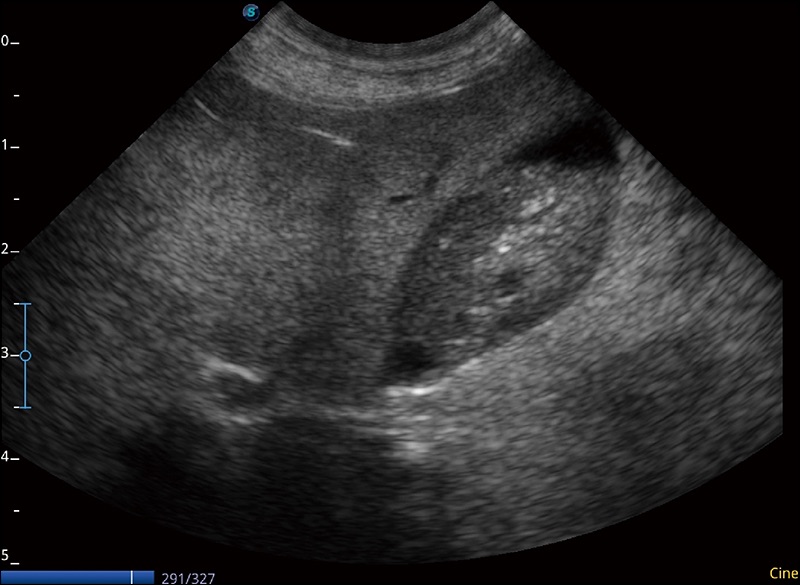

α1卓越的图像质量和便捷的工作流程,使每位宠物医生都能轻松扫查。其全面的兽用应用功能和紧凑型的结构设计,可以满足动物检查的多种需要。专业的预设检查模式和多领域测量软件包有助于为不同类型的动物提供检查, 让宠物医生能够出色的完成工作。

任意波束合成技术

在不牺牲时间分辨率的情况下提供出色的图像

空间复合成像

优化不同角度的图像

实时宽景成像

可实时观察感兴趣区域和病变位置